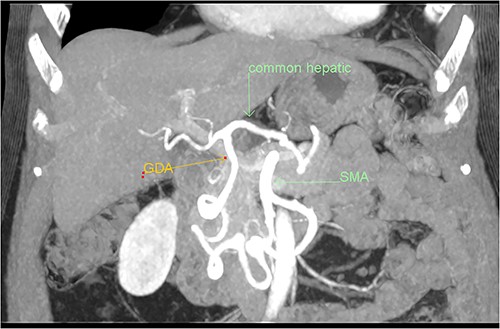

A multiphase CT of the pancreas had unexpected findings. There were no pancreatic masses on the arterial and portal phase study, and no paraaortic or mesenteric lymphadenopathy. The abnormal calcification seen on the previous study corresponded to a dilated vessel along the superior margin of the pancreatic body. This dilated vessel was an abnormal communication between a tortuous ecstatic gastroduodenal artery and the first branch of the SMA, a Buhler’s arc communication. The celiac axis origin was narrowed >90%. No other suspicious solid organ mass lesion was identified. Soft tissues were unremarkable (Figs 5–8).

Multiphase CT pancreas, coronal view: the gastroduodenal artery, off the common hepatic, communicating with the first branch of the SMA.